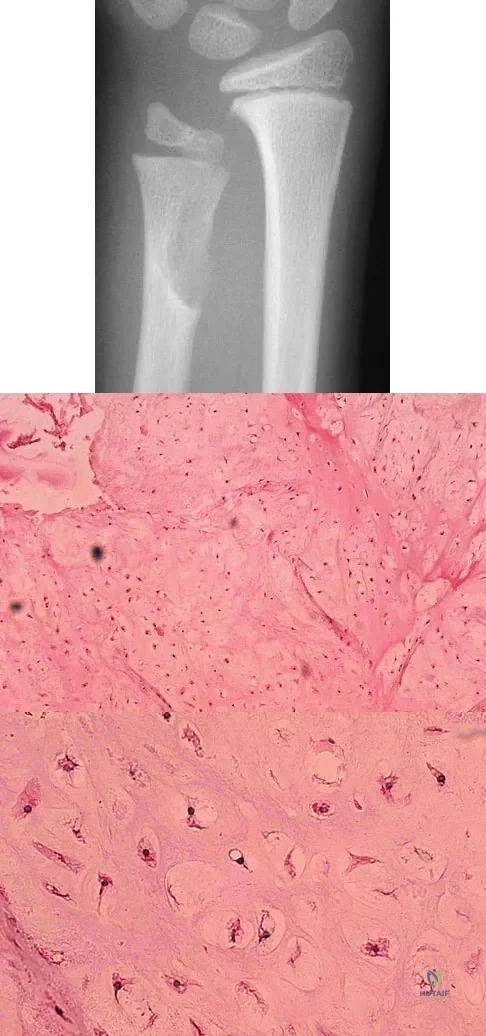

A 10-year-old boy has had wrist pain for the past 3 months. He denies any history of trauma. He reports mild tenderness associated with a palpable mass. A radiograph and biopsy specimens are shown in Figures 52a through 52c. What is the most likely diagnosis?

Explanation